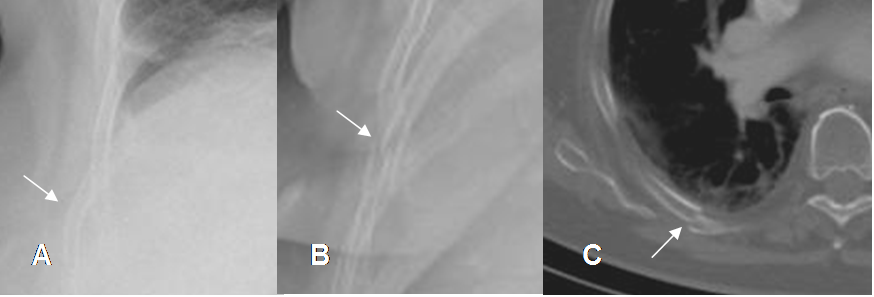

Fig 23. Fractura costal.

A: Rx PA. Irregularidad en el arco costal, con prominencia del cojinete graso, lo que hace sospechar fractura.

B: Rx oblicua y C: TAC axial. Interrupción en la cortical, por fractura levemente desplazada.